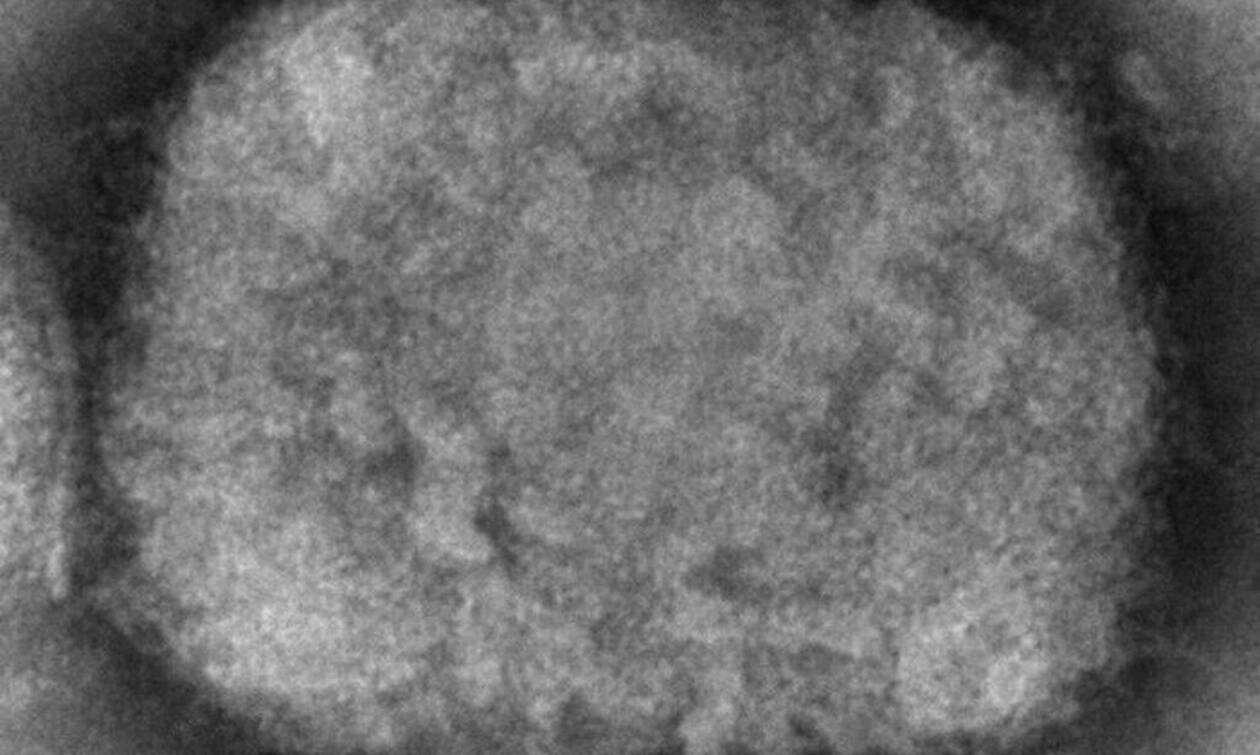

Οι υγειονομικές αρχές της Βραζιλίας επιβεβαίωσαν χθες Σάββατο το δεύτερο κρούσμα ευλογιάς των πιθήκων στη χώρα. Αφορά έναν 29χρονο, ο οποίος έφθασε πριν από λίγες ημέρες στη Βραζιλία από την Ισπανία, σύμφωνα με σχετική ανακοίνωση.

Ο ασθενής τέθηκε σε καραντίνα στην πόλη Βινιέδο, καθώς ενημερώθηκε από εργαστήριο της Ισπανίας ότι διαγνώστηκε θετικός μετά την άφιξή του στη Βραζιλία την Τετάρτη, όπως ανέφεραν οι υγειονομικές αρχές του Σάο Πάολο.

Το πρώτο επιβεβαιωμένο κρούσμα ευλογιάς των πιθήκων στη Βραζιλία καταγράφηκε την Πέμπτη, επίσης στο Σάο Πάολο. Αφορούσε έναν 41χρονο, ο οποίος είχε ταξιδέψει πρόσφατα σε Ισπανία και Πορτογαλία. Βρίσκεται σε καθεστώς απομόνωσης.

Το υπουργείο Υγείας της Βραζιλίας αναφέρει ότι άλλα οκτώ «ύποπτα» κρούσματα ευλογιάς των πιθήκων βρίσκονται υπό διερεύνηση.

Περισσότερα από 1.000 εργαστηριακά επιβεβαιωμένα κρούσματα της ευλογιάς των πιθήκων έχουν αναφερθεί στον Παγκόσμιο Οργανισμό Υγείας από 29 χώρες του κόσμου, σύμφωνα με όσα δήλωσε την Τετάρτη ο γενικός διευθυντής του ΠΟΥ Τέντρος Αντανόμ Γκεμπρεγέσους σε συνέντευξη Τύπου.